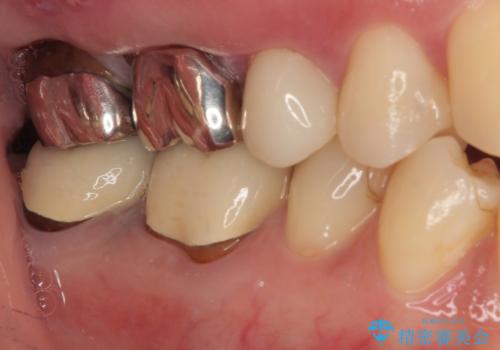

完成したセラミックインレーは精度が高く、適合性に優れているため、歯と調和した自然な仕上がりとなります。

適合の良い詰め物は、二次齲蝕のリスクが低いです。